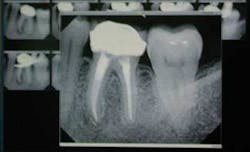

The truth is, their parents love it, too. And that’s the second patient education benefit my digital radiography system brings to me. Parents are much more accepting of my treatment recommendations, because they can see very clearly any caries or lesions or cracks in their children’s teeth. The fact that their children are engrossed in “helping” me with the diagnosis doesn’t hurt their acceptance either. Speaking of diagnosis, we have all had the experience of our patients’ X-rays deteriorating over time (Figure 4). This does not happen with digital X-rays.